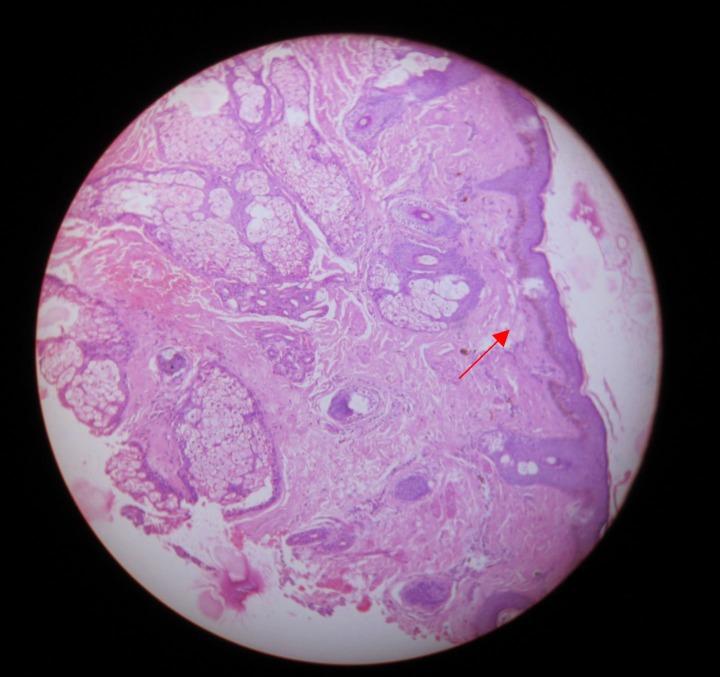

Several occupational hazards especially exposure to silica have been implicated as causal factors for the development of scleroderma-like disorders. Many case reports have documented the co-existence of silicosis and progressive systemic sclerosis in the same patient, mostly from European countries and also from Japan and the United States. We report a case of a 26-year-old male involved in stone masonry who developed silicosis-induced diffuse parenchymal lung disease and systemic sclerosis after exposure to silica dust. To our knowledge, it is the second case to be reported from India.

几种职业危害因素,尤其是接触二氧化硅,已被认为是硬皮病样疾病发生的致病因素。许多病例报告记录了同一患者同时存在矽肺和进行性系统性硬化症,这些病例大多来自欧洲国家,也有来自日本和美国的。我们报告一例26岁从事石匠工作的男性病例,该患者在接触二氧化硅粉尘后患上了矽肺引起的弥漫性实质性肺疾病和系统性硬化症。据我们所知,这是印度报告的第二例此类病例。